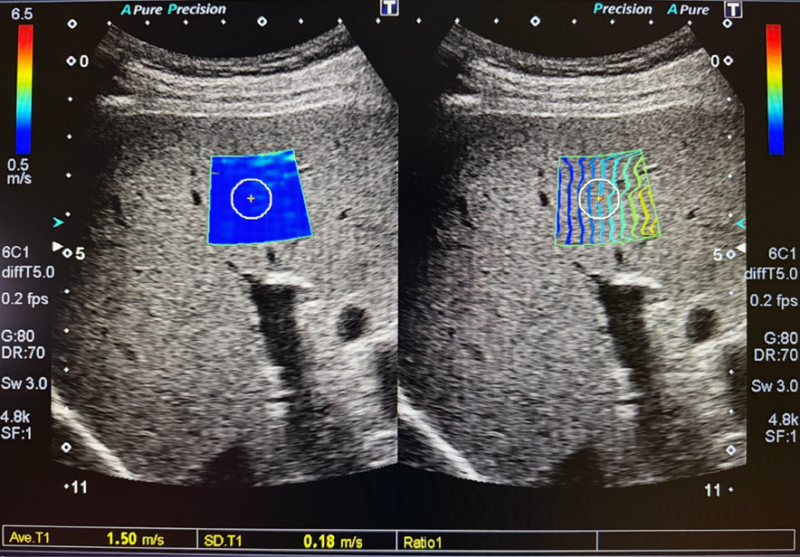

健康診断で脂肪肝(肝機能異常)を指摘されたら、まずは消化器内科などの医療機関を受診しましょう。血液検査(FIB-4 indexなどの線維化マーカー)や腹部エコー検査、肝硬度測定を行い、「ただの脂肪肝なのか」「すでに炎症や線維化が進んでいるMASHなのか」を正しく評価することがスタートです。

脂肪肝は、将来の大きな病気を防ぐための大切なサインです。 健康診断で「脂肪肝」や「肝機能異常」を指摘されたら、無症状だからと自己判断で放置せず、まずは当院のエコー検査で肝臓の「本当の硬さ(線維化の程度)」を正確に評価しましょう。早期に対策を行えば、健康な肝臓を取り戻すことが十分に可能です。